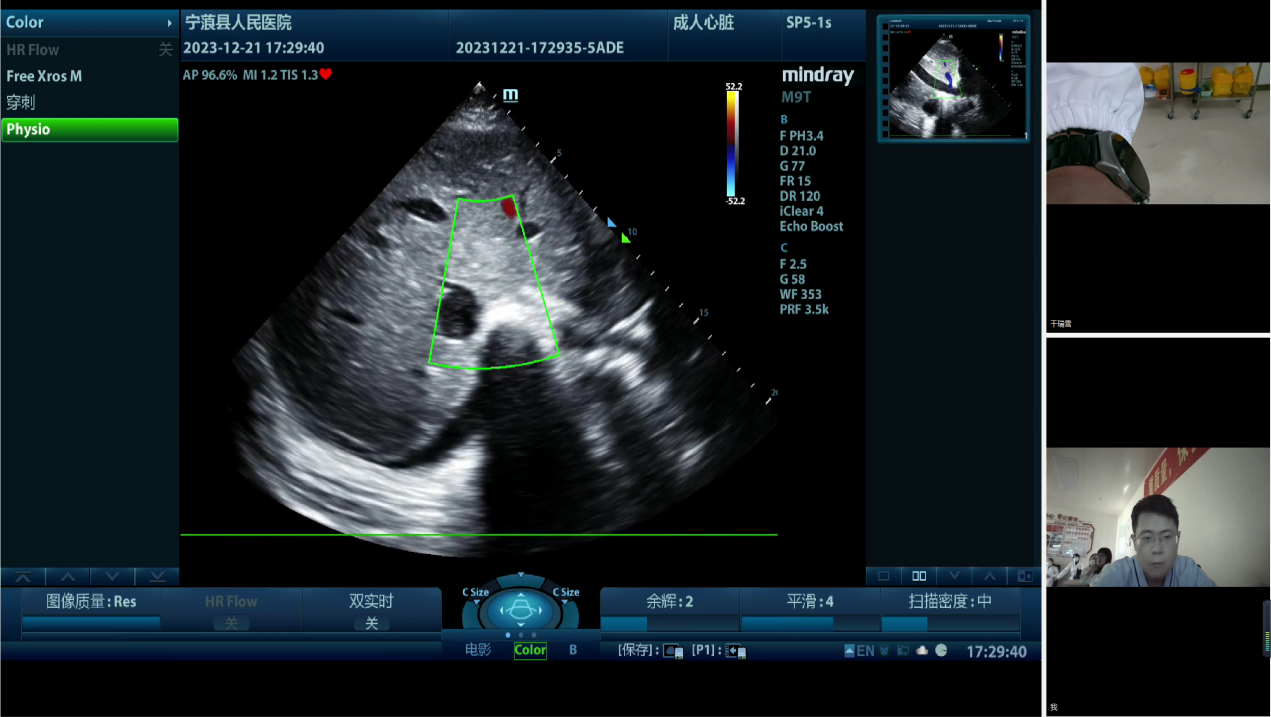

为进一步讨论治疗方案,宁蒗彝族自治县人民财神捕鱼 重症医学科通过“重症超声远程质控会诊平台”邀请财神捕鱼 、丽江市人民财神捕鱼 重症医学科专家及院内专家多学科联合会诊。财神捕鱼 重症医学科万林骏教授、万晓红主任医师、朱炜华副主任医师分别针对循环、呼吸、器官保护等提出治疗建议,并与丽江市人民财神捕鱼 重症医学科陈一峰科主任等专家讨论了下一步优化治疗的方案。